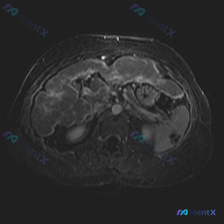

被误判的脾脏病变?这张MRI的真正焦点其实在肝脏

今天看到一张挺有意思的腹部MRI-T2轴位图像,临床初步疑问是“脾脏病变”,但仔细看完觉得思路需要扭转一下,整理出来和大家讨论。

- 序列与质量:T2WI,液体(胆汁、胃液、腹水)呈高信号;有明显呼吸运动伪影,前壁和部分器官边缘模糊,细节观察受一定影响。

- 大家关注的脾脏:形态基本正常,T2信号很均匀,没有看到明确的局灶性高低信号影或占位效应。

- 真正的异常点在肝脏:肝实质信号欠均匀,有多发、结节状信号改变,边界模糊,是不规则的略高或混杂信号,不是单纯的囊肿样“亮”,而是有实性/浸润性的感觉。

- 其他伴随征象:肝肾隐窝和腹腔有少量高信号积液;腹膜后、肠系膜有条片状高信号,脂肪间隙稍显模糊;胰腺、胆囊(腔内高信号,无明确充盈缺损)未见明确局灶异常,胃腔内有液体。